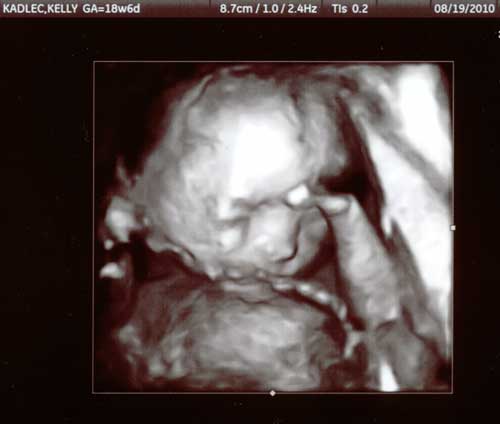

At our 19 week ultrasound appointment,

he looks a little camera shy with his hand in front of his face